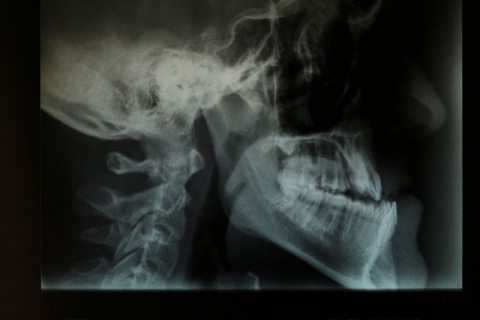

Στο ιατρείο του χρησιμοποιούνται όλες οι σύγχρονες τεχνικές της ορθοδοντικής, προς όλες τις ηλικίες και με όλα τα είδη μηχανισμών, όπως εξωτερικά και εσωτερικά άγκιστρα (brackets), μεταλλικά και διαφανή, κινητοί μηχανισμοί (μασκάκια).

Επίσης, διατίθενται διαφανείς νάρθηκες (τρυγμού, κροταφογναθικού συνδρόμου), λειτουργικά μηχανήματα και παρέχεται αόρατη ορθοδοντική (Invisalign).

Οι σύγχρονες τεχνικές μέθοδοι, σε συνδυασμό με την αδιάλειπτη επιστημονική ενημέρωση και την πολυετή εμπειρία του ιατρού, τον καθιστούν δικαίως πρωτοπόρο, αφού έχει αγγίξει τον ύψιστο στόχο του να μην παραπέμψει, έως και σήμερα, κανένα περιστατικό ασθενούς σε χειρουργική επέμβαση (ορθογναθικά περιστατικά).